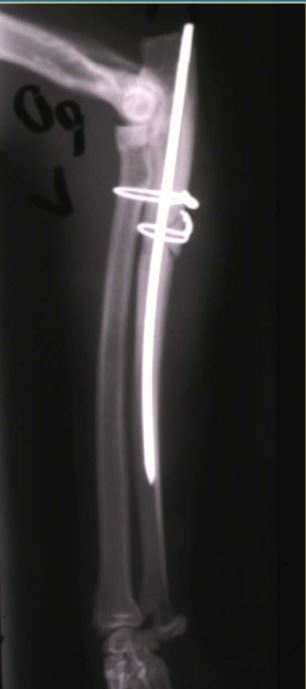

4 month old canine, 10kg

HBC 24 hours ago

Classify and assess fracture, and give repair options

A

Long oblique fracture of the proximal femoral diaphysis

Fx score= 8-10

Repair: IM pin+ cerclage wire, ESF, bone plate